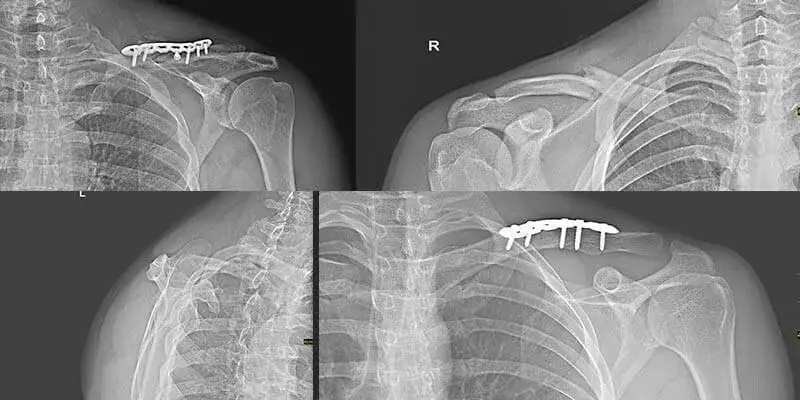

Metoda leczenia ma ogromny wpływ na czas powrotu do zdrowia. Operacje wymagające stabilizacji płytką i śrubą mogą przyspieszyć proces, ponieważ pacjenci często wracają do normalnego funkcjonowania już po 1-2 dniach. Natomiast w przypadku złamań leczonych zachowawczo, czas rehabilitacji może być dłuższy, ponieważ pacjenci muszą poczekać na zdjęcie unieruchomienia, co zazwyczaj trwa od 3 do 6 tygodni.

Rehabilitacja po złamaniach z przemieszczeniem jest bardziej skomplikowana i wymaga dłuższego czasu, zazwyczaj od 6 do 12 miesięcy. Tego rodzaju złamania często wymagają interwencji chirurgicznej, co wpływa na czas powrotu do zdrowia. Po operacji, pacjent może rozpocząć normalne funkcjonowanie już 1-2 dni po zabiegu, jednak pełna rehabilitacja zaczyna się dopiero po kilku tygodniach. W tym czasie ważne jest, aby pacjent przestrzegał zaleceń lekarza i unikał nadmiernego obciążania kończyny.